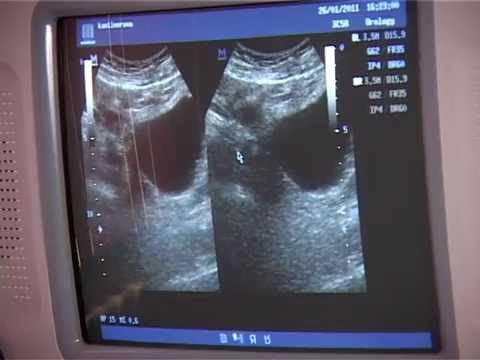

Hellow guys, Welcome to my website, and you are watching Как быстро растут полипы?. and this vIdeo is uploaded by Медицинский центр «Династия» at 2025-02-11T01:26:39-08:00. We are pramote this video only for entertainment and educational perpose only. So, I hop you like our website.